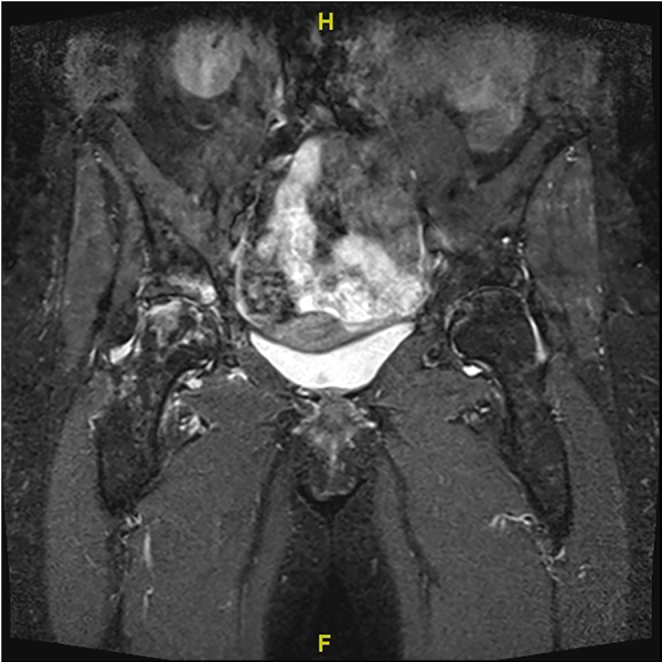

酪氨酸钾尿症是一种极其罕见的酪氨酸代谢疾病,由常染色体隐性遗传的同源戊二酸(HGA)氧化酶缺乏症引起,会导致酪氨酸在胶原结构中蓄积,尤其是在透明软骨中。该病的特征是同型戊二酸尿症、结缔组织蓝黑色褪色(chronosis)以及脊柱和大型负重关节的关节病。该病有多种临床表现,包括冠状动脉和瓣膜钙化、主动脉狭窄、胸部扩张受限、肾结石、尿道结石和前列腺结石以及眼部和皮肤色素沉着。骨骼病变通常表现为脊柱的脊椎病变。膝关节是最常见的受累外周关节。可能会出现腱鞘炎或肌腱断裂,骨密度降低也并不罕见。低蛋白饮食和抗坏血酸可降低 HGA 水平。尼替西酮可以安全有效地减少 HGA 的产生和尿液排泄。对于严重的chronotic关节病,关节置换术可提供可靠的疼痛缓解和良好的功能效果。对年轻患者来说,无水泥固定是一种成功的方法。

Alkaptonuria is an extremely rare disorder of tyrosine metabolism caused by an autosomal recessive enzymatic deficiency of homogentisic acid (HGA) oxidase, causing its accumulation in collagenous structures, especially in hyaline cartilage. It is characterized by a triad of homogentisic aciduria, bluish-black discoloration of connective tissues (ochronosis) and arthropathy of the spine and large weight-bearing joints. Several clinical manifestations were described including coronary and valvular calcification, aortic stenosis, limited chest expansion, and renal, urethral and prostate calculi as well as ocular and cutaneous pigmentation. Skeletal affection usually presents as spondylotic changes of the spine. The knee is the most common peripheral joint to be involved. Enthesopathy or tendon ruptures may occur, and reduced bone density is not unusual. A low-protein diet and ascorbic acid may reduce HGA levels. Nitisinone can safely and effectively reduce HGA production and urinary excretion. In severe ochronotic arthropathy, joint arthroplasty can offer reliable pain relief and excellent functional outcomes. Cementless fixation is successful in young patients.